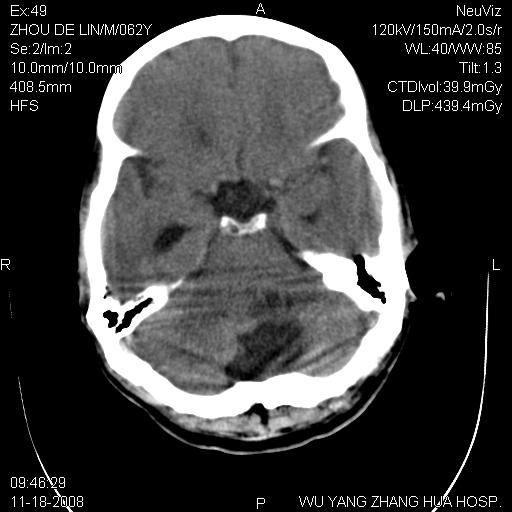

患者近段时间偶有头晕,无其他不适。既往有糖尿病病史。

小脑中线区见一类圆形混杂密度影,四脑室受压变形,其后方见一边界清楚的囊性低密度影,幕上脑室扩张。小脑中线区肿瘤,儿童多见于髓母细胞瘤,成人多见于胶质瘤。

诊断:小脑胶质瘤可能性大。建议增强扫描

小脑囊实性占位病变、脑室系统积水扩张、脑肿胀。

小脑囊实性占位病变、脑室系统积水扩张,建议增强

诊断:小脑胶质瘤可能性大。建议增强扫描。支持!

1)小脑蚓部(偏左侧)占位性病变;不排除转移瘤可能。建议行进一步检查。2)脑积水。